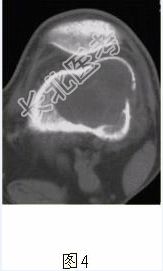

- [材料题] 患者女,35岁,左膝关节隐痛1年余,近1周加重,活动后明显疼痛。查体:左股骨下端外侧肿胀,压痛。行左膝关节正侧位CR,并行左膝关节CT扫描,见下图。

- 简答题1、根据膝关节CR和CT影像,你认为此病例的影像学表现有?

- 简答题2、对本病例,应首先考虑的诊断是?